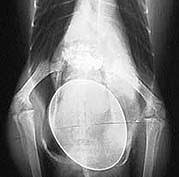

Calcium is nodig voor stevige botten en skelet en het maken van een eischaal, maar ook voor de het goed functioneren van spieren en zenuwstelsel. Bij een tekort aan calcium tijdens het opgroeien van een jonge papegaai zien we skeletafwijkingen die bekend staat als Rachitis of Engelse ziekte.

De grijze roodstaart is hiervoor extra gevoelig.